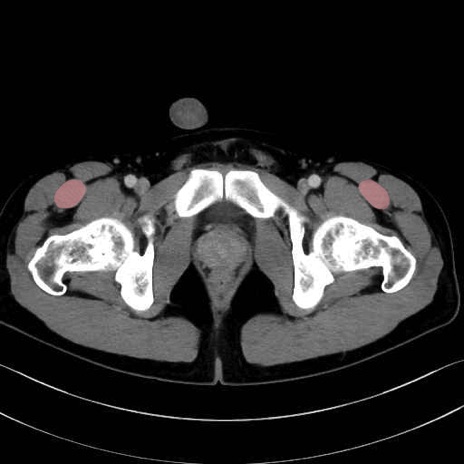

大腿直筋 (Rectus femoris)